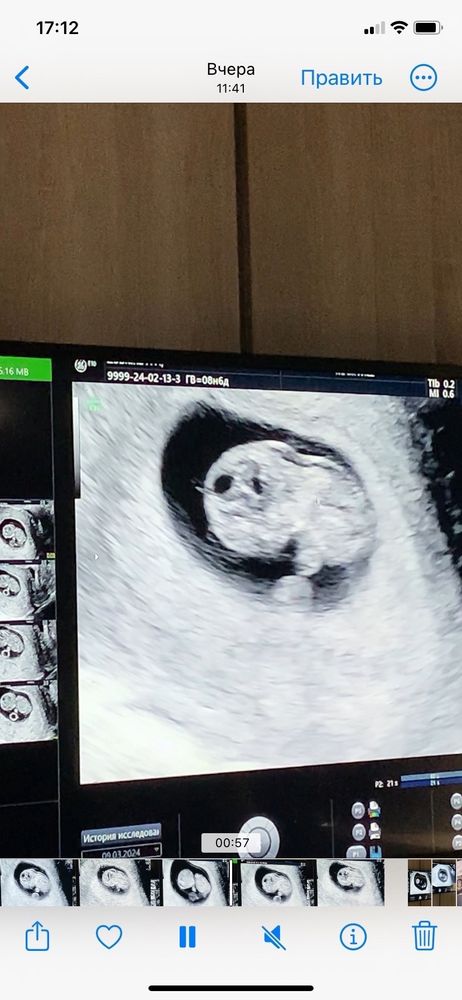

Узи 9 недель

Катерина , ой, я вообще без понятия 😄 Она сказала, что развивается хорошо, отслоек нет. Потом зачем - то навела на воротниковое пространство, сказала про него, но что увеличено не сказала. Сказала мол, что лучше бы пораньше скрининг сделать, на 12-13 неделе, чтобы посмотреть на наличие к ХА, вот так вот) Может я её не так поняла, но мне показалось, что что - то не так по её виду и выражению лица. Врач хорошая, главный врач в этой платной клинике, поэтому и расстроилась как - то. Сейчас у меня уже срок 9.4, а то узи было сделано в 8.6, так и хочется ещё раз на узи сходить до скрининга 😁 Не могу, нервничаю слишком из-за этого

Там же вообще еще крошка какой твп мерить,у меня был такой же карапуз на 9 неделе.В 12+5 по скринингу твп 1,5 и все шикарно.Вам рано разводить панику,дождитесь скрининга 🥰

Рано ещё для данного показателя. Дождитесь скрининга)))все хорошо с вашим мальчонком( по поводу пола чисто мои предложения по данным фото)